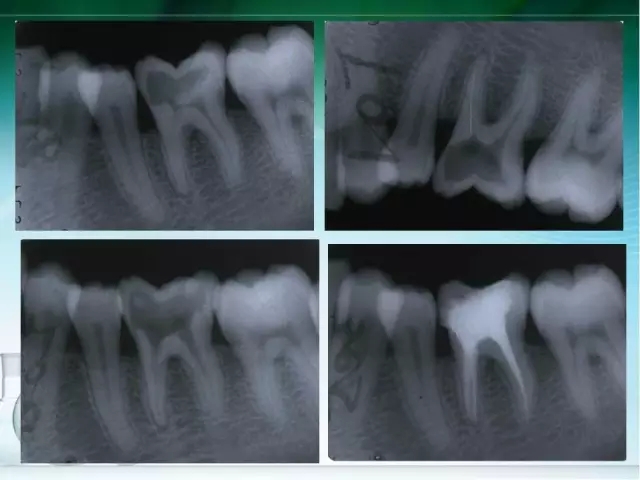

此文關(guān)鍵字:根管治療并發(fā)癥及處理